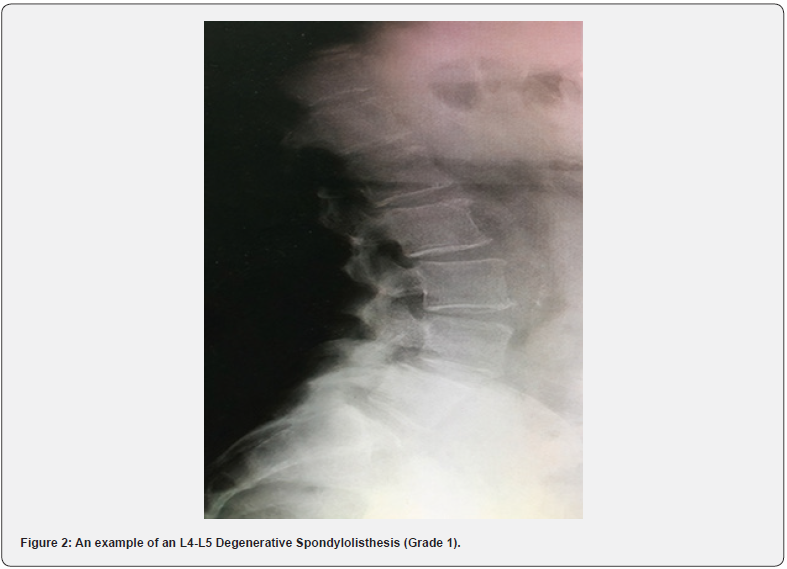

The patient population that was under investigation, which resulted in a total of 1,000, included 61 cases with a mean age of ∼55 years (54.7) that were identified with spondylolisthesis. With a confidence interval of 95% (0.119), the prevalence of spondylolisthesis was 6.1% (±0.119) of the true value. In addition, the Male to Female ratio that has been reported in the study is 20:41 i.e. (1:2). Females are twice as likely to have this disorder than males. The highest frequency of spondylolisthesis was degenerative spondylolisthesis (66%), followed by isthmic spondylolisthesis (30%), and dysoplastic spondylolisthesis (5%) (Figure 3). The vertebral level L5-S1 was the most common level involved (56%) with L4-L5 level involved in 37% (Figure 4) in comparison to most studies concerning spondylolisthesis [2-4] (Figures 1 & 2). Lower back pain was reported in 92% of those with spondylolisthesis, with a confidence interval of 95% (1.679%) and ~92% (91.80%) ± 1.679% from the true interval). Unfortunately, there is inconclusive evidence of a correlation between spondylolisthesis and occupation. The prevalence ratio was not calculated, as there were insufficient data. The study’s main aim was to not only determine the prevalence and link lower back pain to this disorder but also to identify any other associated risk factors that might have an impact on this disorder. There seems to be no exact or definite indication for a single disease/ disorder that may be considered a factor that might result in the development of spondylolisthesis. However, (CI 95%) 13 out of 61 (21 ± 2.11%) patients with spondylolisthesis also had a history of hypertension, (CI 95%) 16 out of 61 (26.23% ± 1.95%) patients with spondylolisthesis who had a history of Diabetes Mellitus, and (CI 95%) 7 of the 61 (11.475 ± 2.27%) patients had hypothyroidism, but the question is, are these chronic illnesses the reason for the increased risk of this disorder? Because of the nature of these systemic illnesses, they can affect the prognosis of this disorder; however, are critical risk factors that have a distinct effect on this specific disorder. Simply put, there is little evidence to support this theory. Regarding the patients’ lifestyle, since Kuwaiti population is one of the top ten ranked countries in regards to obesity and being overweight, most patients that were studied are not exercising as an average individual, which is 150 min of aerobic exercise per week. The majority of patients lived a sedentary lifestyle in addition to a poor nutritional diet.

Various aspects were considered when developing the methodology. The inclusion criteria played a significant role in differentiating this study from others. An effort was made to incorporate all types of spondylolisthesis, and not restricting the age limit, to obtain an overview of the actual prevalence of spondylolisthesis. In addition, other factors in the methodology that were considered were the use of standing radiographs as a means to confirm the diagnosis in comparison to MRI or CT scans. The reasoning behind this was that radiographs (anterior/ posterior and lateral X-rays) were more sensitive in the ability to pick up a grade 1 spondylolisthesis (Meyerding classification of 0-25%) [11] versus other modalities of investigations that required the patient to lie down, limiting the opportunity to establish a proper diagnosis.